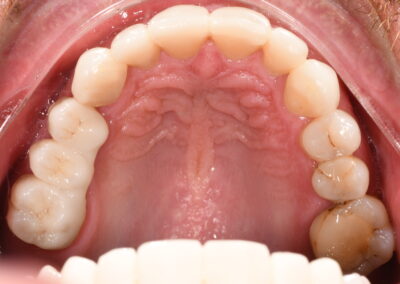

To improve the function and appearance of the front teeth, direct resin restorations were used. These restorations effectively treated areas of decay while maintaining a natural aesthetic and preserving the structural integrity of the teeth.

The treatment resulted in a successful restoration of the patient’s oral health, functionality, and aesthetics. Decay was effectively managed, and the patient’s gum disease was brought under control through ongoing periodontal care. The direct resin restorations on the front teeth provided a natural appearance and improved the patient’s confidence in their smile. The placement of tooth-supported bridges on the upper right, upper left, and lower right quadrants, along with implant-supported bridges, restored full chewing function, enhanced stability, and improved overall oral structure. The patient is now on a regular maintenance program to ensure long-term success and continued oral health.